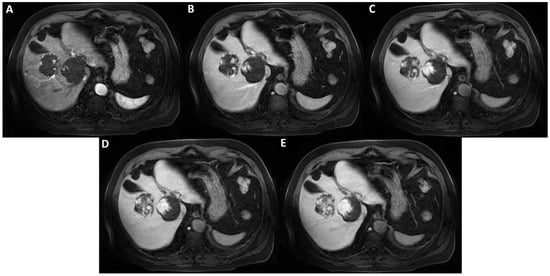

Axial T1-weighted fat saturated images after hepatospecific contrast agent (Gd-EOB-DTPA) administration in arterial, portal-venous, and delayed phases (A–E) show early peripheral discontinuous globular enhancement of the lesions with progressive centripetal filling-in on delayed scans. This angiodynamic behavior supports the diagnosis of cavernous hemangiomas.